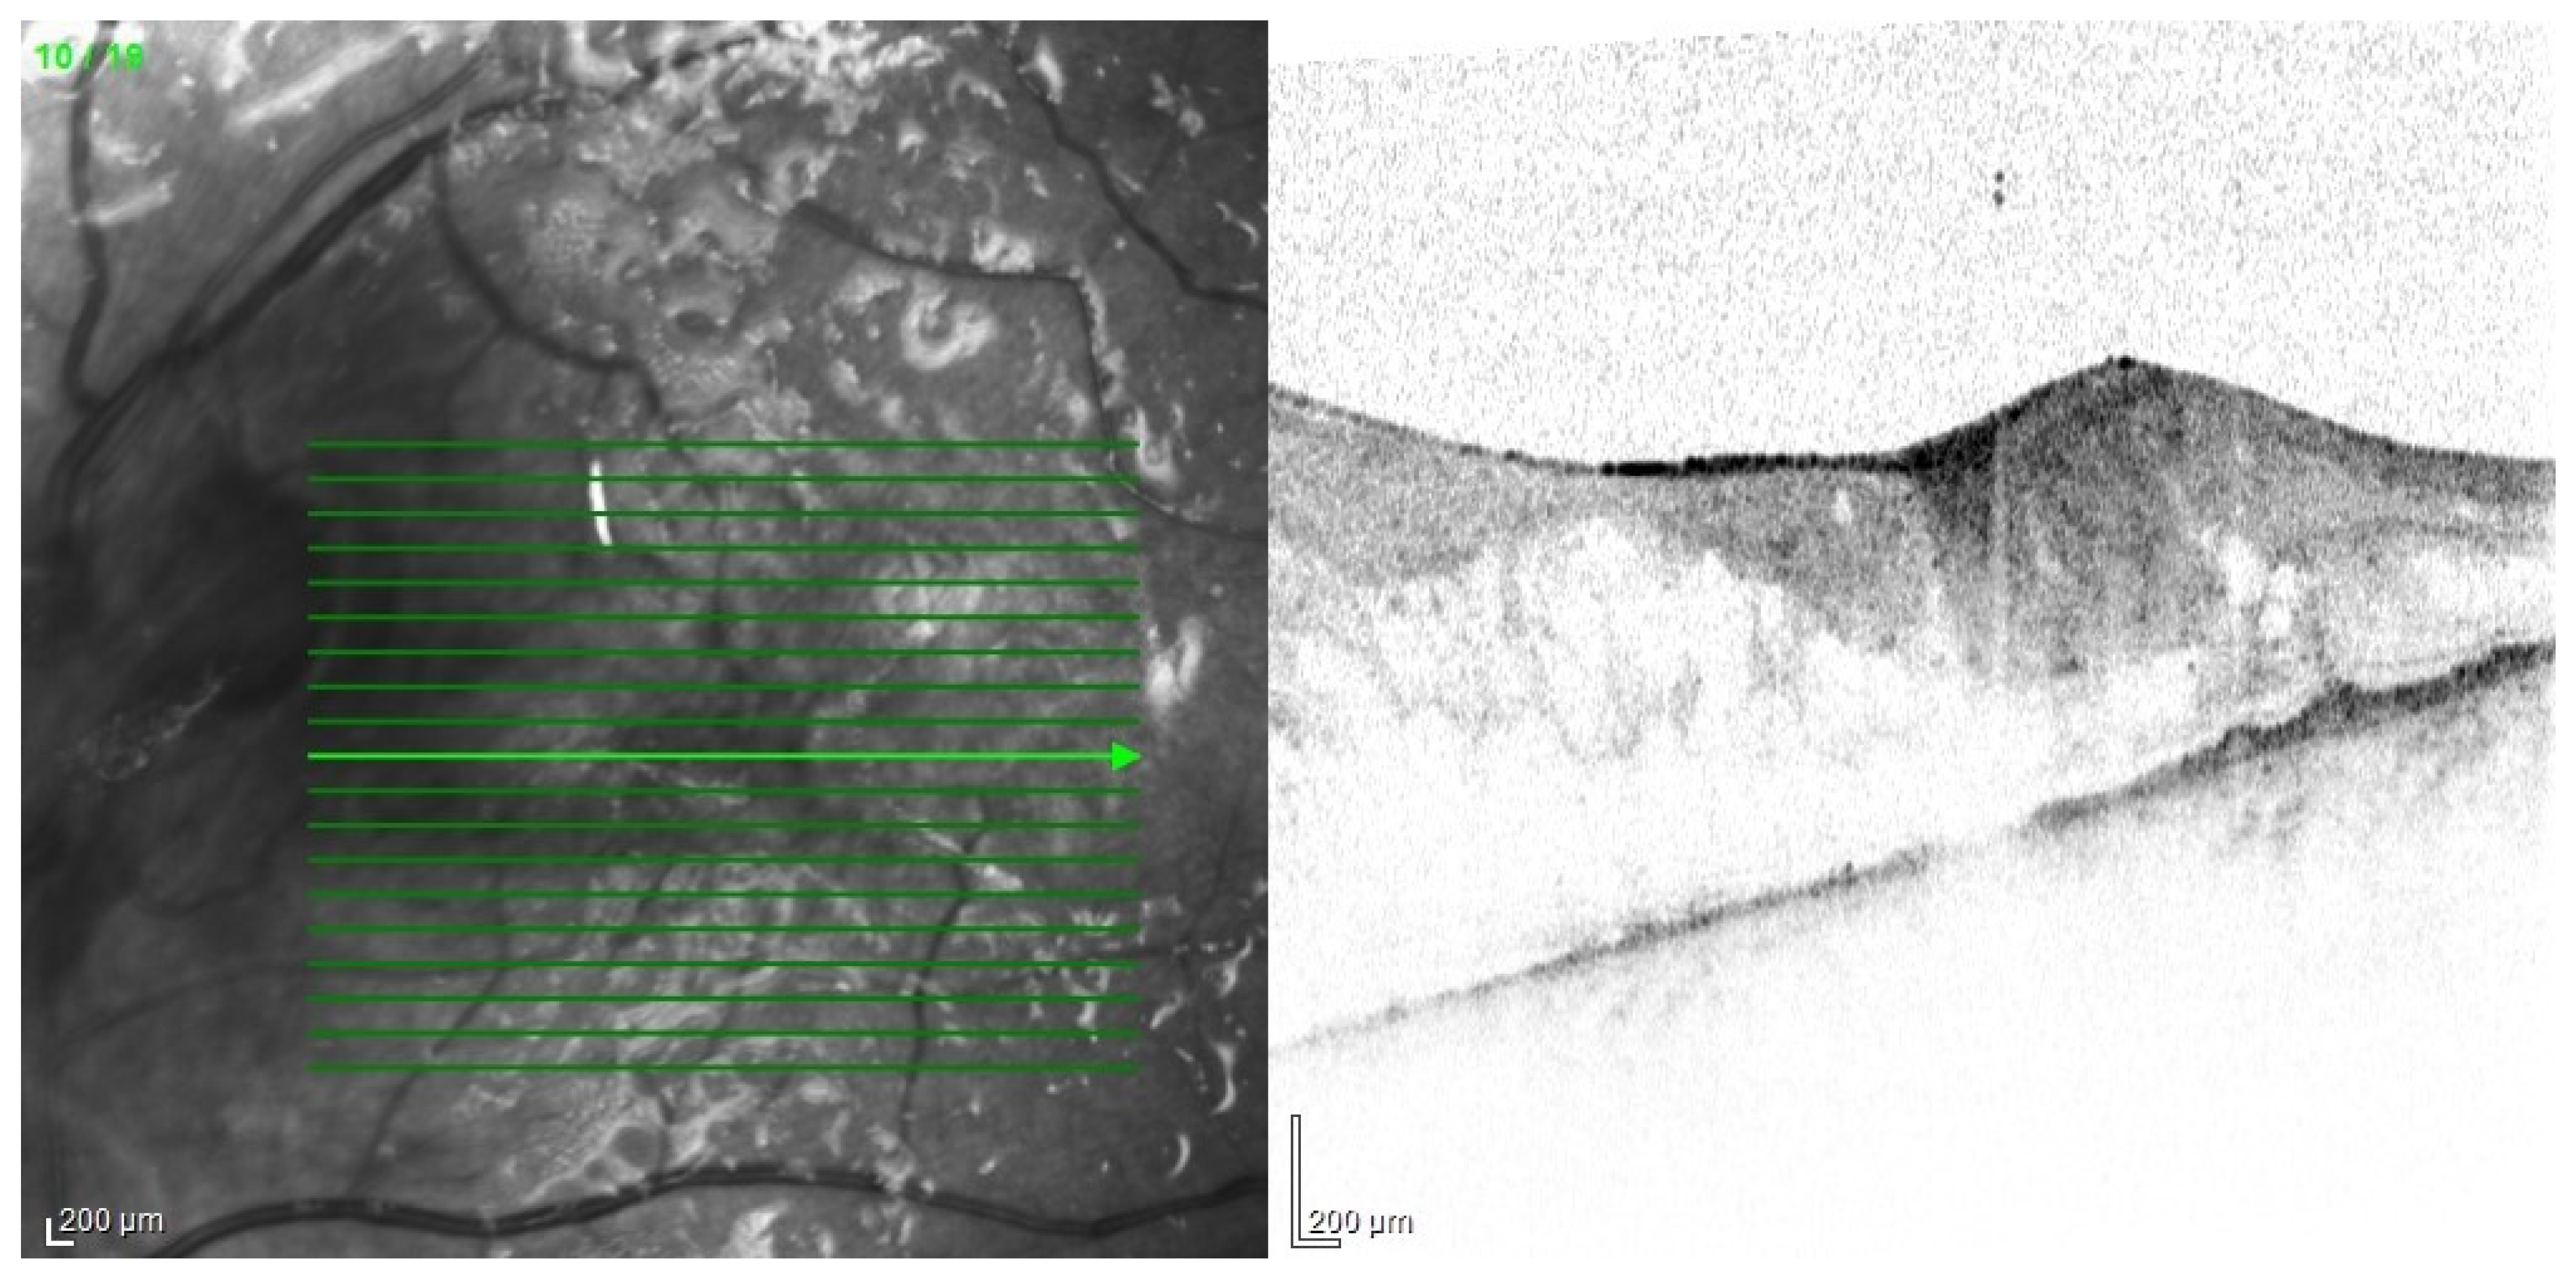

The main problem in patients after endophthalmitis is the damage to the retina, especially atrophy and remodeling of retinal layers, which disrupts its function and worsening visual acuity [89]. Changes can be very accurately imaged in optical coherence tomography (Figure 13). In addition, dysfunction of the pigment epithelium and abnormalities of the blood–retinal barrier can lead to persistent macular edema (Figure 14).

Figure 13.

OCT scan with extensive structural changes in the retina. Visible atrophic changes, the remodeling of the layers of the retina, and intraretinal edema in the temporal part.

Figure 14.

Condition after vitrectomy with silicone oil endotamponade. Persistent edema of the macular area seen on OCT.

A much more serious complication of intense inflammation is the development of proliferative vitreoretinopathy. Membranes that make retina stiffer may lead to its tractional detachment. In advanced cases, it may be necessary to perform recurrent vitrectomy (Figure 15, Figure 16 and Figure 17).

Figure 15.

Photo of the optic nerve area, a vitreous chamber filled with silicone oil. Visible massive fibrous proliferation on the optic nerve disc and subretinal proliferations, lifting the retina.

Figure 16.

OCT examination of the patient presented in Figure 15. Cross-section of the optic disc area. Visible retinal elevation due to the presence of fibrosis.

Figure 17.

OCT examination of the patient presented in Figure 15. The macular area of the left eye. OCT shows tractional retinal folds, epiretinal membranes, cystic spaces, and disorganization of the retinal layers.